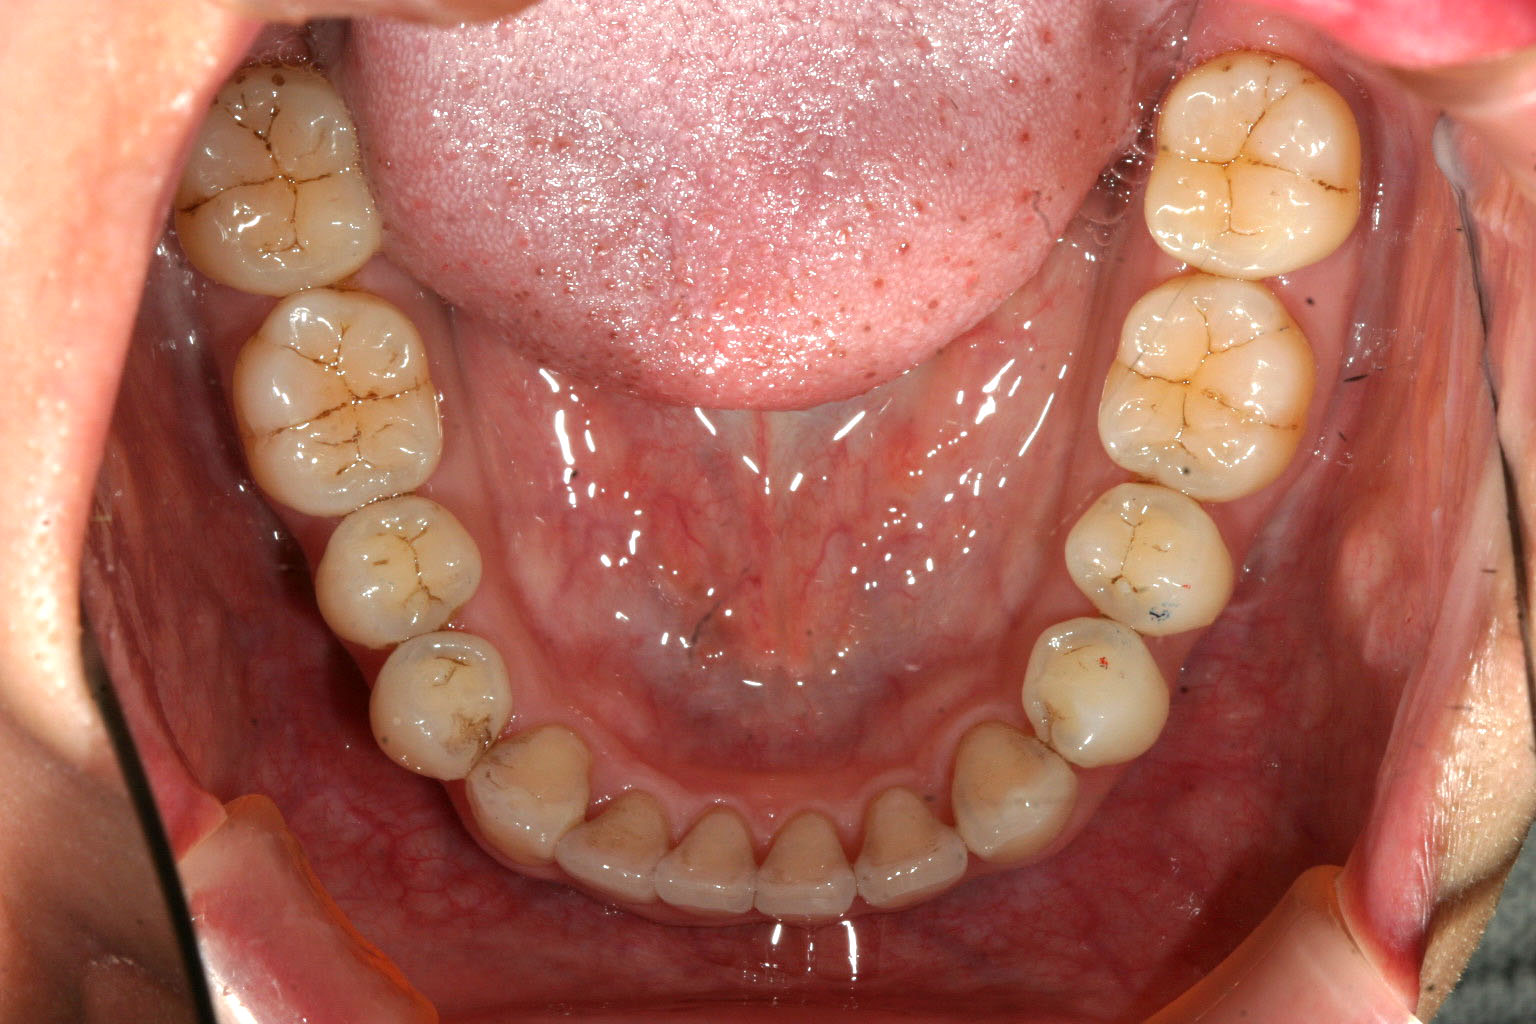

右側の犬歯の飛び出しが目立ちます。

下顎のアーチが狭い為に叢生が目立ちます。

側面観もガタガタが目立ちます。